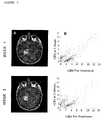

FIG. 8 shows (A) receiver operator characteristic curves for VD(solid line) and VI(small dashed line) from PRMrCBFand % rCBF (large dashed line) forweeks 1 post-treatment and (B) Kaplan-Meier survival plot for overall survival are presented as a function of VDfrom PRMrCBFstratification atweeks 1 post-treatment. Solid line indicates VD≦cutoff and dotted line indicates VD>cutoff (cutoff=4.15%; p=0.001).

FIG. 8A shows receiver operator characteristic curves for VD(solid line) and VI(small dashed line) from PRMrCBFand % rCBF (large dashed line) forweeks 1 post-treatment. VDwas found to be significantly predictive of survival at one year with an ROC_AUC of 0.704 (cutoff=4.15%, p=0.021). VIand % rCBF generated an ROC_AUC of 0.567 and 0.511, respectively. Kaplan-Meier survival plot,FIG. 8B, for overall survival is presented as a function of VDfrom PRMrCBFstratification atweeks 1 post-treatment. Solid line indicates VD≦cutoff and dotted line indicates VD>cutoff (cutoff=4.15%; p=0.001).